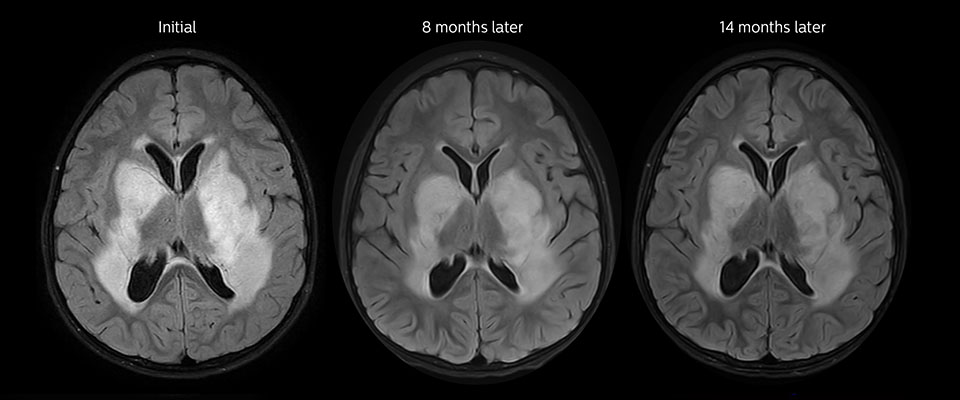

MRI with APT post resection

Immediately post resection MRI was again performed. T2-weighted and postcontrast T1-weighted images are quite inconclusive for distinguishing residual tumor tissue from postoperative tissue changes. On the APT image some high signal is still seen, which would suggest residual tumor tissue.

Follow-up over time

In later follow-up scans the post-contrast T1-weighted images suggest recurrent tumor growth. So, it would be interesting to study the predictive value of APT in a large patient group.